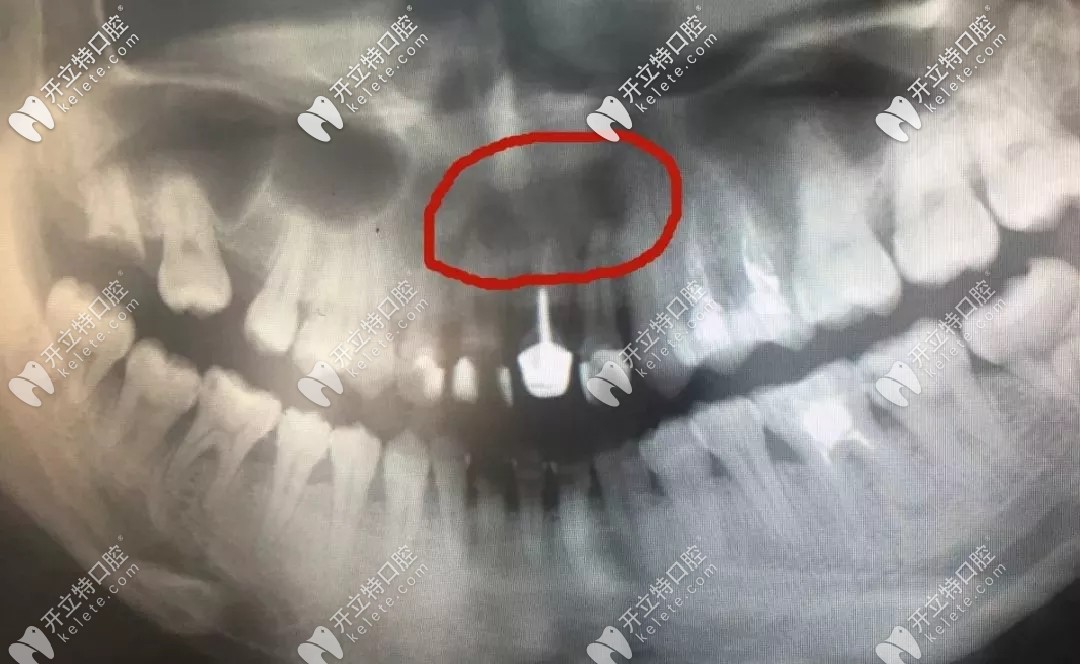

牙根尖的囊腫

▲牙根尖的囊腫